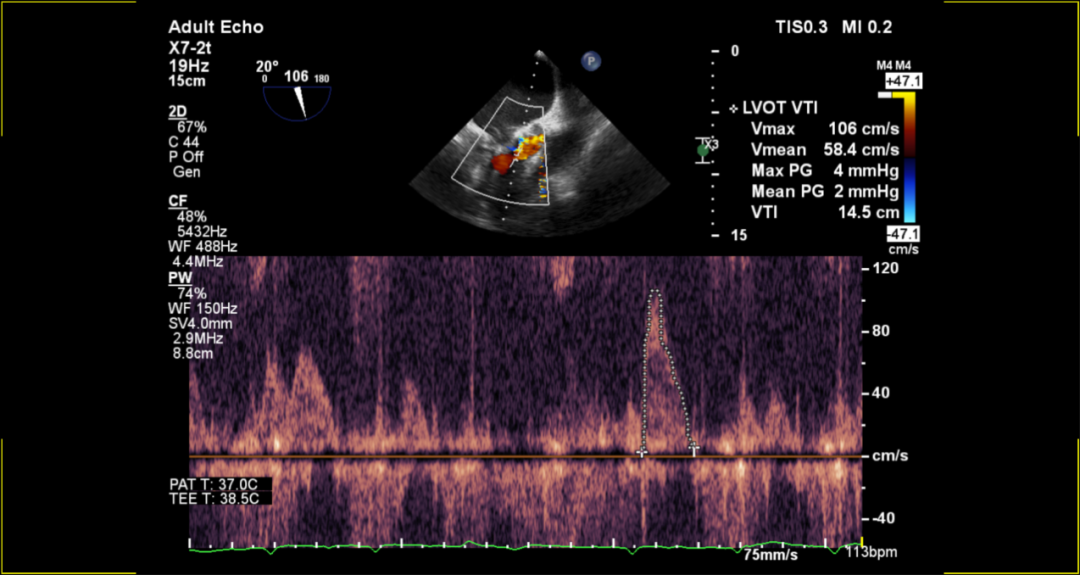

术后超声评估:

术后无反流、左室流出道通畅